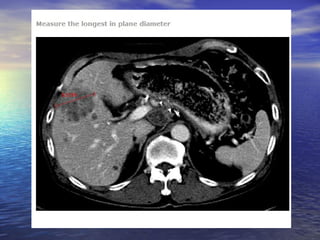

Diferença da avaliação em relação à fase do contraste

fase arterial                           Fase portal